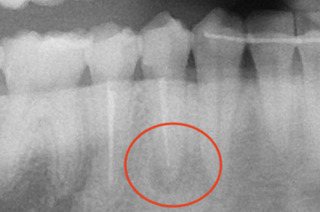

レントゲン。

赤丸の部分が根尖部分の透過像。黒くなっていると思います。

が、思ったより綺麗。でもなぜ根尖部に感染による透過像があるのか(レントゲンの黒いやつね)

もしや‥もう一つ根管があるのかも?!

と思い、狭い歯の中を拡大していくと‥

やはりありました。もう一つの根管。

1根じゃなく2根管だったのね。

これで透過像の謎が解けました。